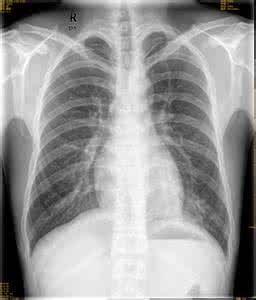

大家对肺炎这个疾病都非常熟悉了,由于恶劣环境的影响,越来越多的人患上了感冒的疾病,因此,肺炎的发病几率也就高了起来。这种疾病已经严重影响到患者的生活和工作了,有关肺炎的常识大家应该了解下。

肺炎症状